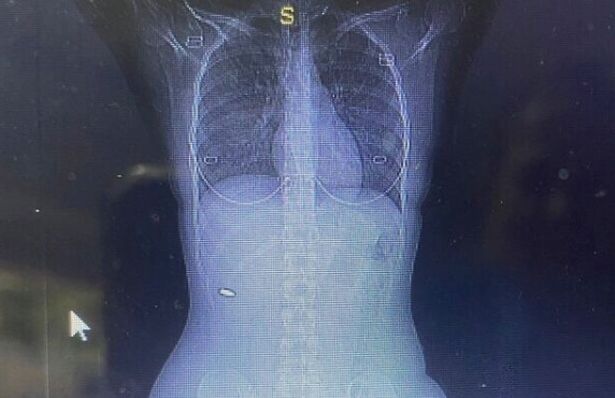

Viên đạn nằm gần cột sống.

3 tháng sau, Bloy vẫn không ngừng cảm thấy đau đớn nên tới bệnh viện kiểm tra. Cô yêu cầu chụp ảnh cắt lớp vi tính (CT), cho thấy có vật thể dạng kim loại gần cột sống.

Sau khi tiến hành phẫu thuật gắp dị vật, các bác sĩ mới nhận ra đó là một viên đạn cỡ 5,56mm, chuyên dùng cho súng trường.